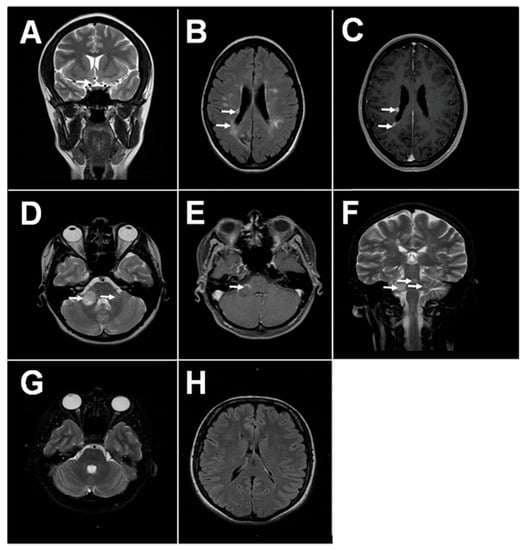

MS pathology is characterized by multiple lesions within the CNS [1]. The pathogenesis of brain lesions remains largely unknown; however, neurodegeneration due to inflammation and immune reaction towards the brain cells is believed to play the central role. Interestingly, brain plaques in MS are predominantly found within the white matter around the lateral ventricles and optic nerve [2,3]. Recently, the presence of the brain plaques in the grey matter was demonstrated by Calabrese et al. [4]. These lesions could be detected early and correlate with the disease severity [5]. Lesions in periventricular locations along the 4th ventricle, midbrain and cerebellar peduncle are also characteristic for MS, though they are less prevalent [6,7]. The close proximity of lesions to the ventricles containing the choroid plexus, a structure of the blood-cerebrospinal fluid (CSF) barrier, suggests a connection between peripheral circulation and brain tissue pathology (Figure 1).

Figure 1. Magnetic resonance imaging (MRI) of MS and health brain. (A) Typical MS lesions in the right optical nerve on coronal T2 image; (B,C) Typical MS lesions in periventricular white matter on axials T2 and T1 post contrast images, respectively; (DF) Typical MS lesions in the white matter of sub-tentorial structures (pons, right middle cerebellar peduncle): on axials T2 and T1-post-contrast, and coronal T2 images, respectively; (G,H) MRI of the healthy adult brain: normal sub-tentorial structures on axial T2 images, normal periventricular white matter on axial FLAIR images, respectively.